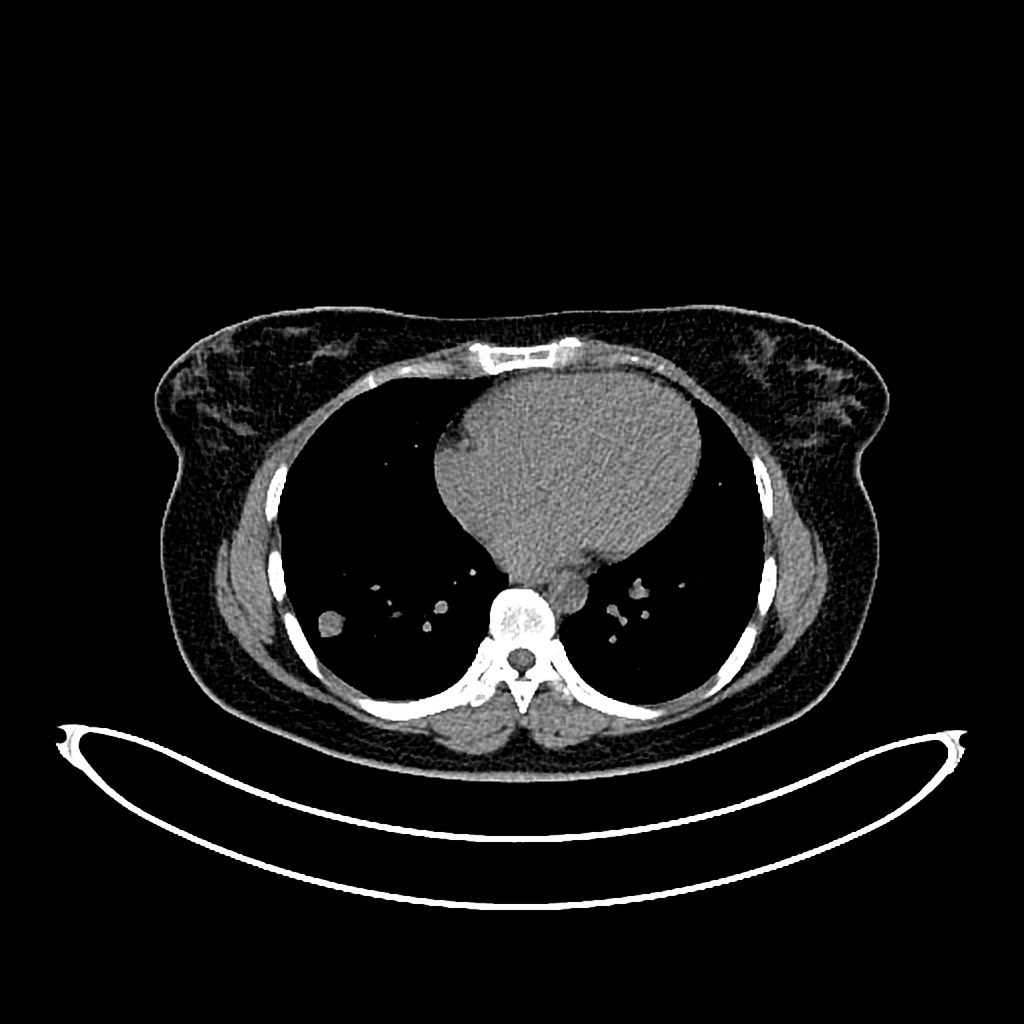

1362. В случае псевдовоспалительной опухоли лёгкого, локализация которой представлена на изображении у пациента пожилого возраста, страдающего инсулиннезависимым сахарным диабетом в стадии субкомпенсации, целесообразно выполнение